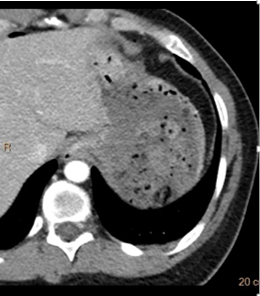

Bullet is retained in subcutaneous tissues of the left upper quadrant. But are there any other injuries?

The stomach wall looks very non-descript on conventional CT. Iodine map shows focal defect. A through and through gastric injury was confirmed on surgery, along with bowel injury. Primary repair of bowel injury and stomach and left nephrectomy was performed. Patient recovered uneventfully.

Iodine overlay image nicely depicts left kidney injury and bowel injury